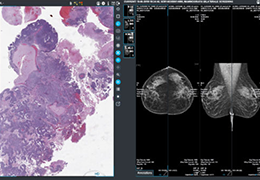

View X-Ray CT & MRI Scans Fast and Easily

Designed for surgeons, Pro Surgical 3D makes it easy to view patient scans quickly. Pro Surgical 3D facilitates the optimal 3D treatment and assessment workflows based on X-ray CT and MRI scans – and best of all, it’s FREE!

Everyone – including surgeons, patients and their loved ones – benefits from being better informed by the wealth of information buried within CT and MRI scans. Pro Surgical 3D gives surgeons more information to develop optimal treatment plans for patients. It also helps patients and their support group better understand their medical condition and proposed treatment options.

Designed mainly for CT and MR DICOM modalities.